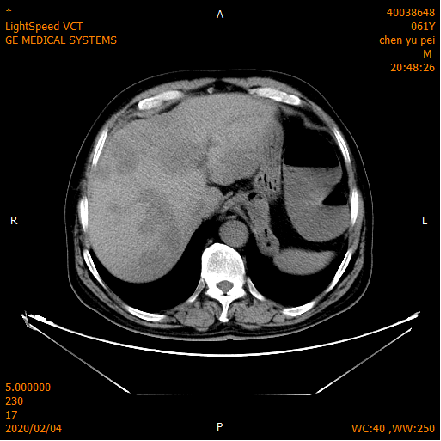

2020-02-04 CT

肝脏多发异常强化灶,考虑转移。

横结肠-降结肠交界处壁增厚强化,请结合消化道检查,腹腔部分肠管扩张积气积液,可见气液平,请结合临床。